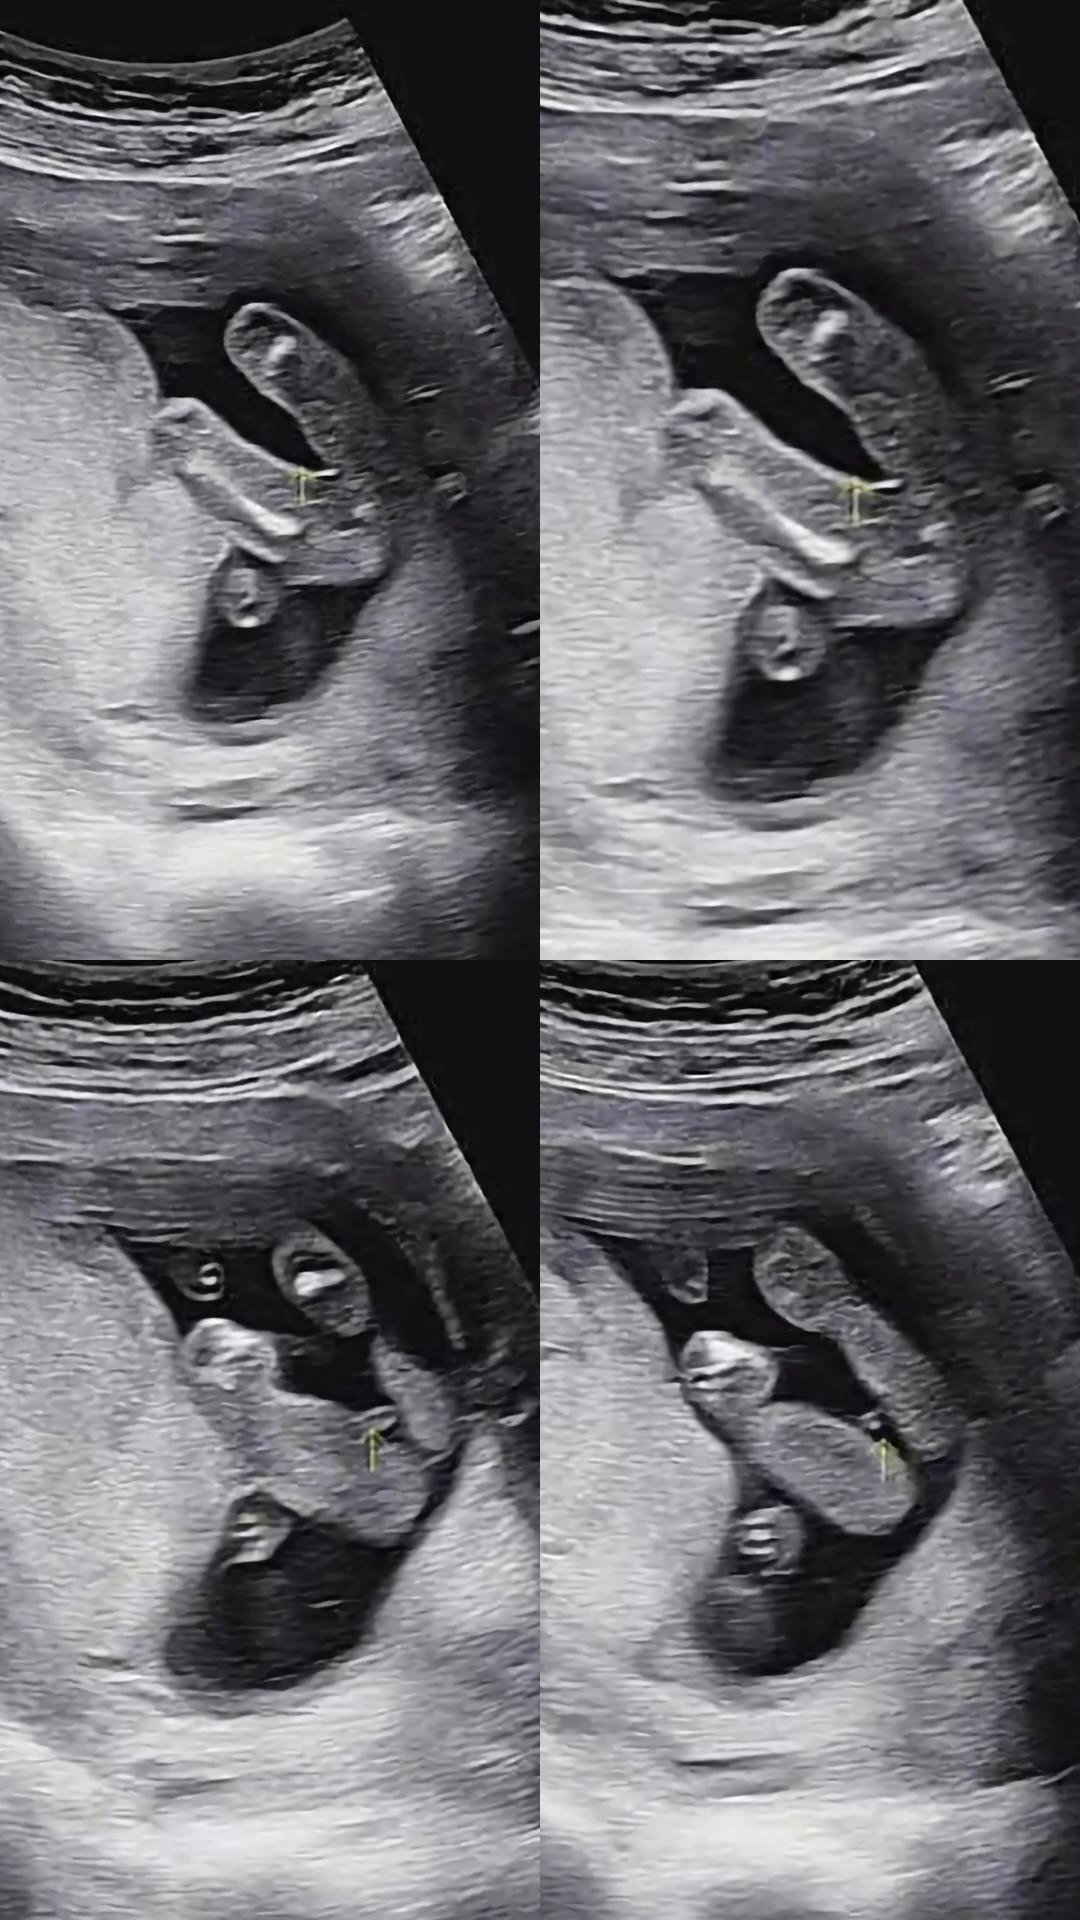

성별 좀 같이봐주세요 ㅠㅠ

16주차인데 진료 보러갔더니 성별을 잘 모르겠다고하시네요 같이 좀 봐주세요ㅠㅜ

제가 보기엔 아들인데요..?